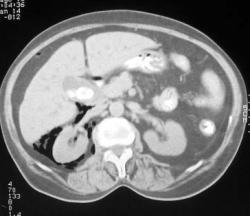

Ретропневмоперитонеум после ПСТ.

Пациентка 70 лет с механической желтухой. Эндоскописты выполнили папиллосфинктеротомию с последующей РХПГ (фатеров сосок был конусовидной формы, никак не получалось заканюлировать, его и рассекли). Немного повредили стенку 12п. кишки, в дефект попал воздух. Всё обошлось без операции, провели курс а/б терапии, воздух рассосался, дефект закрылся. Топограмма напоминает виденные когда-то в учебниках снимки с диагностическим ретропневмоперитонеумом (только воздуха маловато). Сканы в нестандартном окне, чтобы видеть воздух на фоне жировой клетчатки. Воздух скопился преимущественно вокруг правой почки.